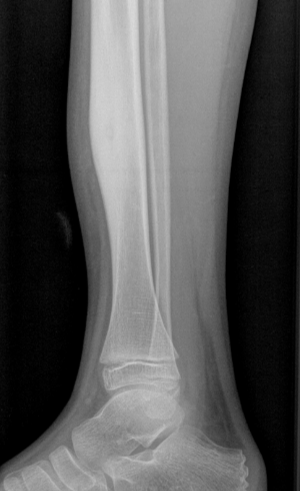

Osteoid osteoma